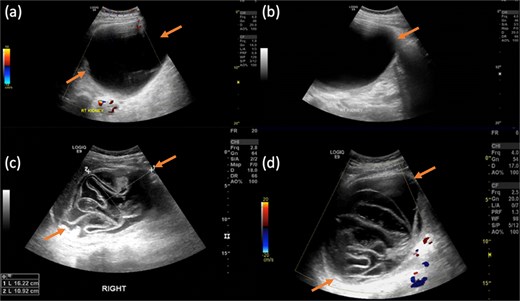

Ultrasound showed a large cystic lesion in the right kidney with internal debris and fluid–fluid levels (Fig. 1). Contrast-enhanced CT confirmed a thick-walled, fluid-filled cyst in the right upper renal pole without septations or calcifications—consistent with recurrent hydatid disease (Fig. 2). Incidentally, a small pelvic cystic lesion was seen adjacent to the rectum and seminal vesicle.

Gray-scale transabdominal ultrasound demonstrates a large well-defined anechoic lesion located in the upper pole of the kidney. The lesion contains internal, non-septated debris and shows no internal vascularity on color doppler imaging (a and b). Compared with previous right renal lesion showing collapsed membranes float within the cyst fluid, resembling water lily.